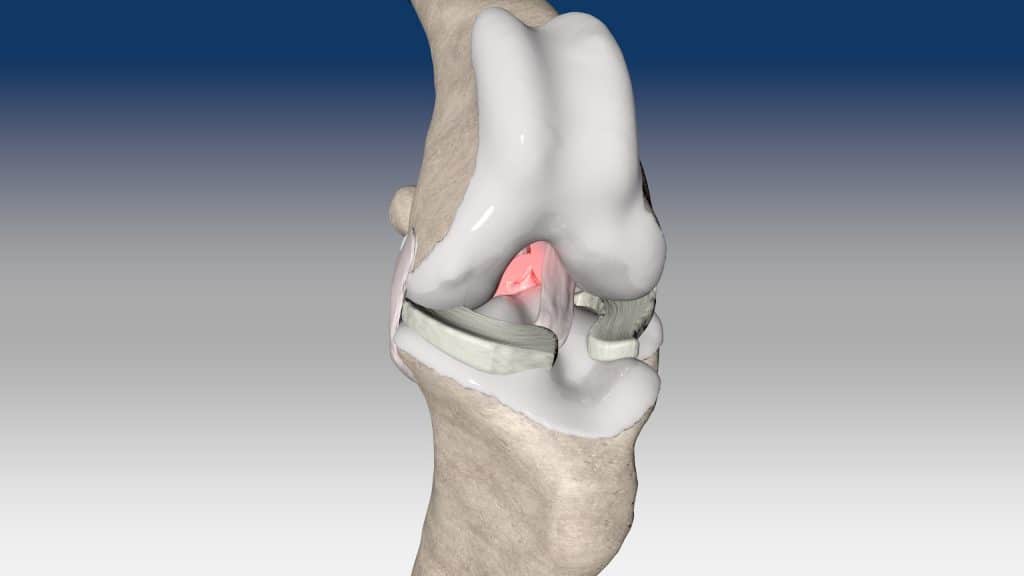

Ruptura kraniálního zkříženého vazu je hlavní příčinou ortopedických konzultací u psů. Tento stav se obvykle léčí chirurgicky pomocí osteotomických technik, mimokloubní stabilizace nebo intraartikulární rekonstrukce.

V případě ruptury kraniálního zkříženého vazu umožňuje ExtraTape® extraartikulární rekonstrukci co nejblíže izometrii původního vazu, čímž rychle a trvale stabilizuje koleno bez uzlů a zvlnění, což je slabina tradičnějších technik extraartikulární stabilizace. Ty jsou zde nahrazeny pevným ukotvením kosti pomocí interferenčního šroubu.

Řešení, které respektuje původní anatomii, obnovuje funkci postiženého vazu a je dostupné v rámci otevřené nebo artroskopické chirurgie.

V případě zkřížených vazů umožňuje intraartikulární rekonstrukci v izometrických bodech připojení, čímž obnovuje biomechaniku kolene a všechny funkce natrženého vazu.